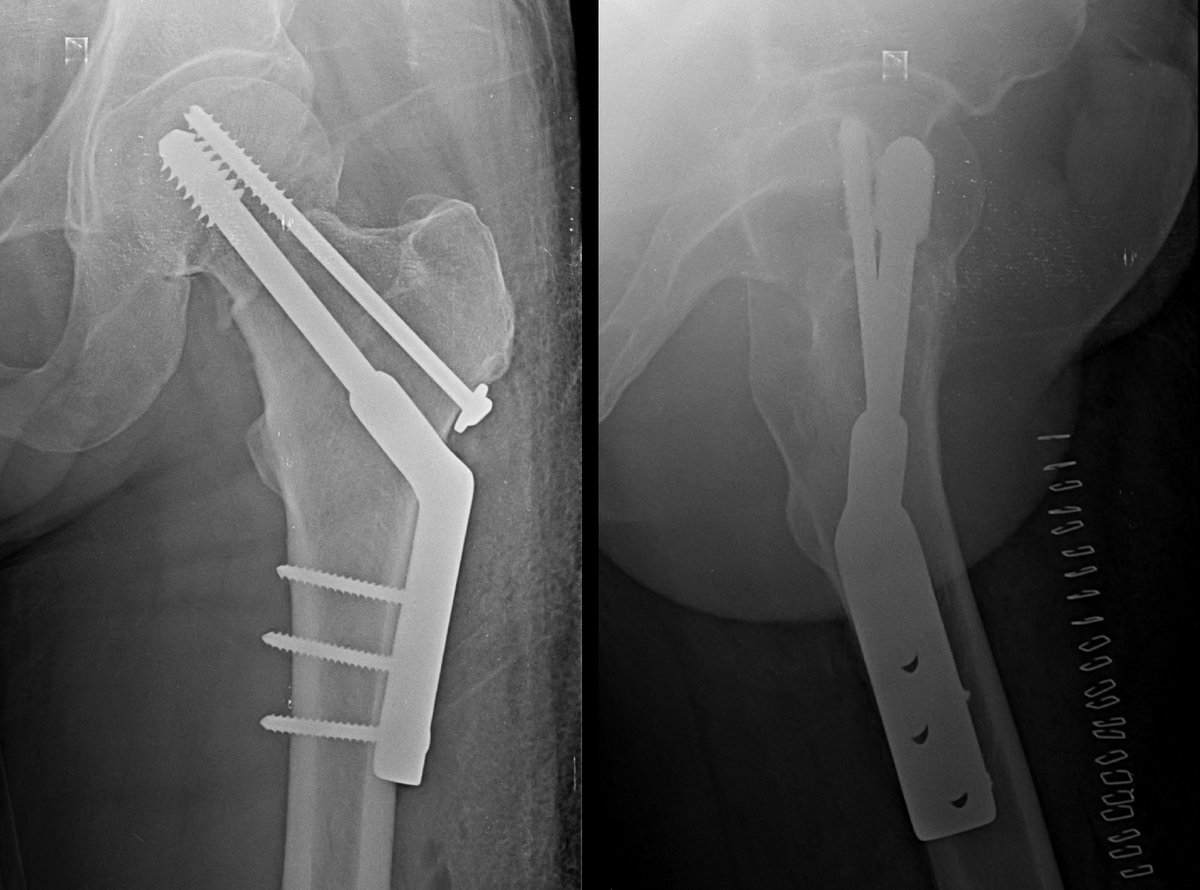

Neck of femur fracture in 55 year old gentleman,

Pauwel type 2

Mild Comminuted !

Did DHS with CC Screw.

#medtwitter #medx #orthotwitter #orthox #fracture

@pratikorho good construct for such a pattern. Without knowing patient factors, THR is not for everyone and has a distinct complication spectrum

the TAD is for IT fractures. using 2 points of fixation controls rotation while providing fixed angle support.

which one is placed first?